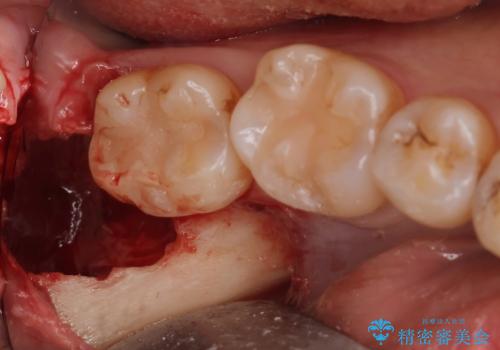

- 親知らずを抜歯したいとの事で来院。

パノラマ,CT撮影を行い安全なことを確認して抜歯を行いました。

抜歯後1週間後に抜糸と消毒を行い処置は完了になります。